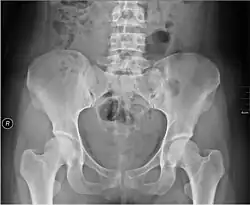

Met de wandbucky worden o.a. opnamen gemaakt van de borstkas en met de tafelbucky o.a. van bekken en buik. Bij gebruik van een strooistralenraster moet de stralendosis een stuk hoger zijn dan wanneer men zonder raster fotografeert om de vereiste beeldhelderheid te verkrijgen.